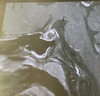

Q

Dx

A

Hematoma subdural